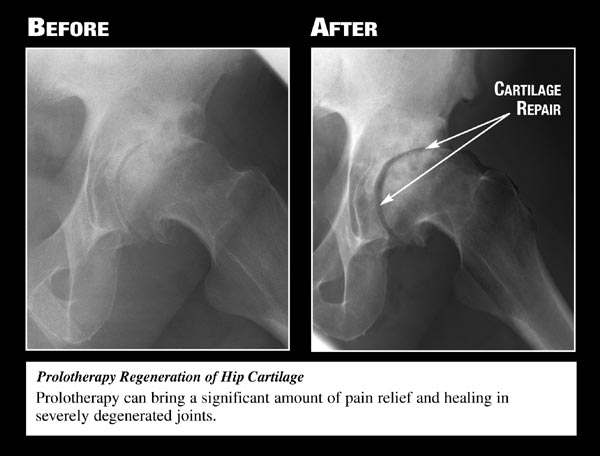

Used

with permission from Ross A Hauser, MD,

www.caringmedical.com.

Prolotherapy involves injections of a mildly irritating

solution into the painful area. The irritant, usually a

dextrose-based solution, triggers the body's natural

healing response and causes the proliferation of new

collagen fibers, which are the building blocks of

ligaments and tendons. (The "prolo" in prolotherapy stands

for proliferative.) As tissue growth continues, the

ligaments and tendons become thicker and stronger,

regaining their ability to stabilize the joint and take

the pressure off sensitive nerve endings. Pain subsides,

range of motion returns, and cartilage degeneration slows

down.